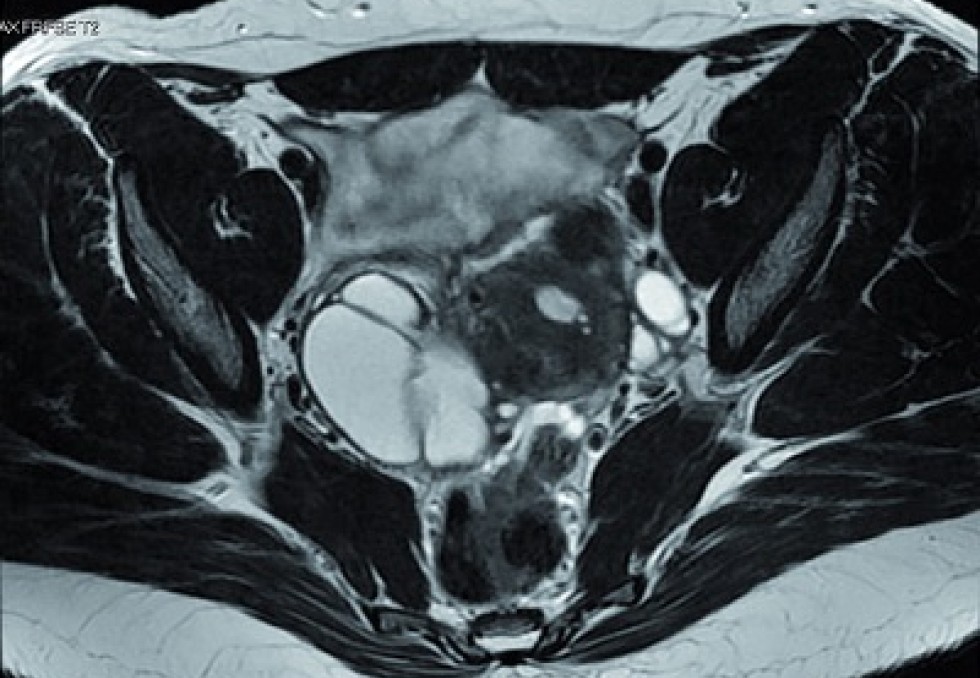

endométriose

Endométriose : vers un remboursement généralisé de l'Endotest ?

Une femme sur dix en âge de procréer est concernée par l’endométriose.